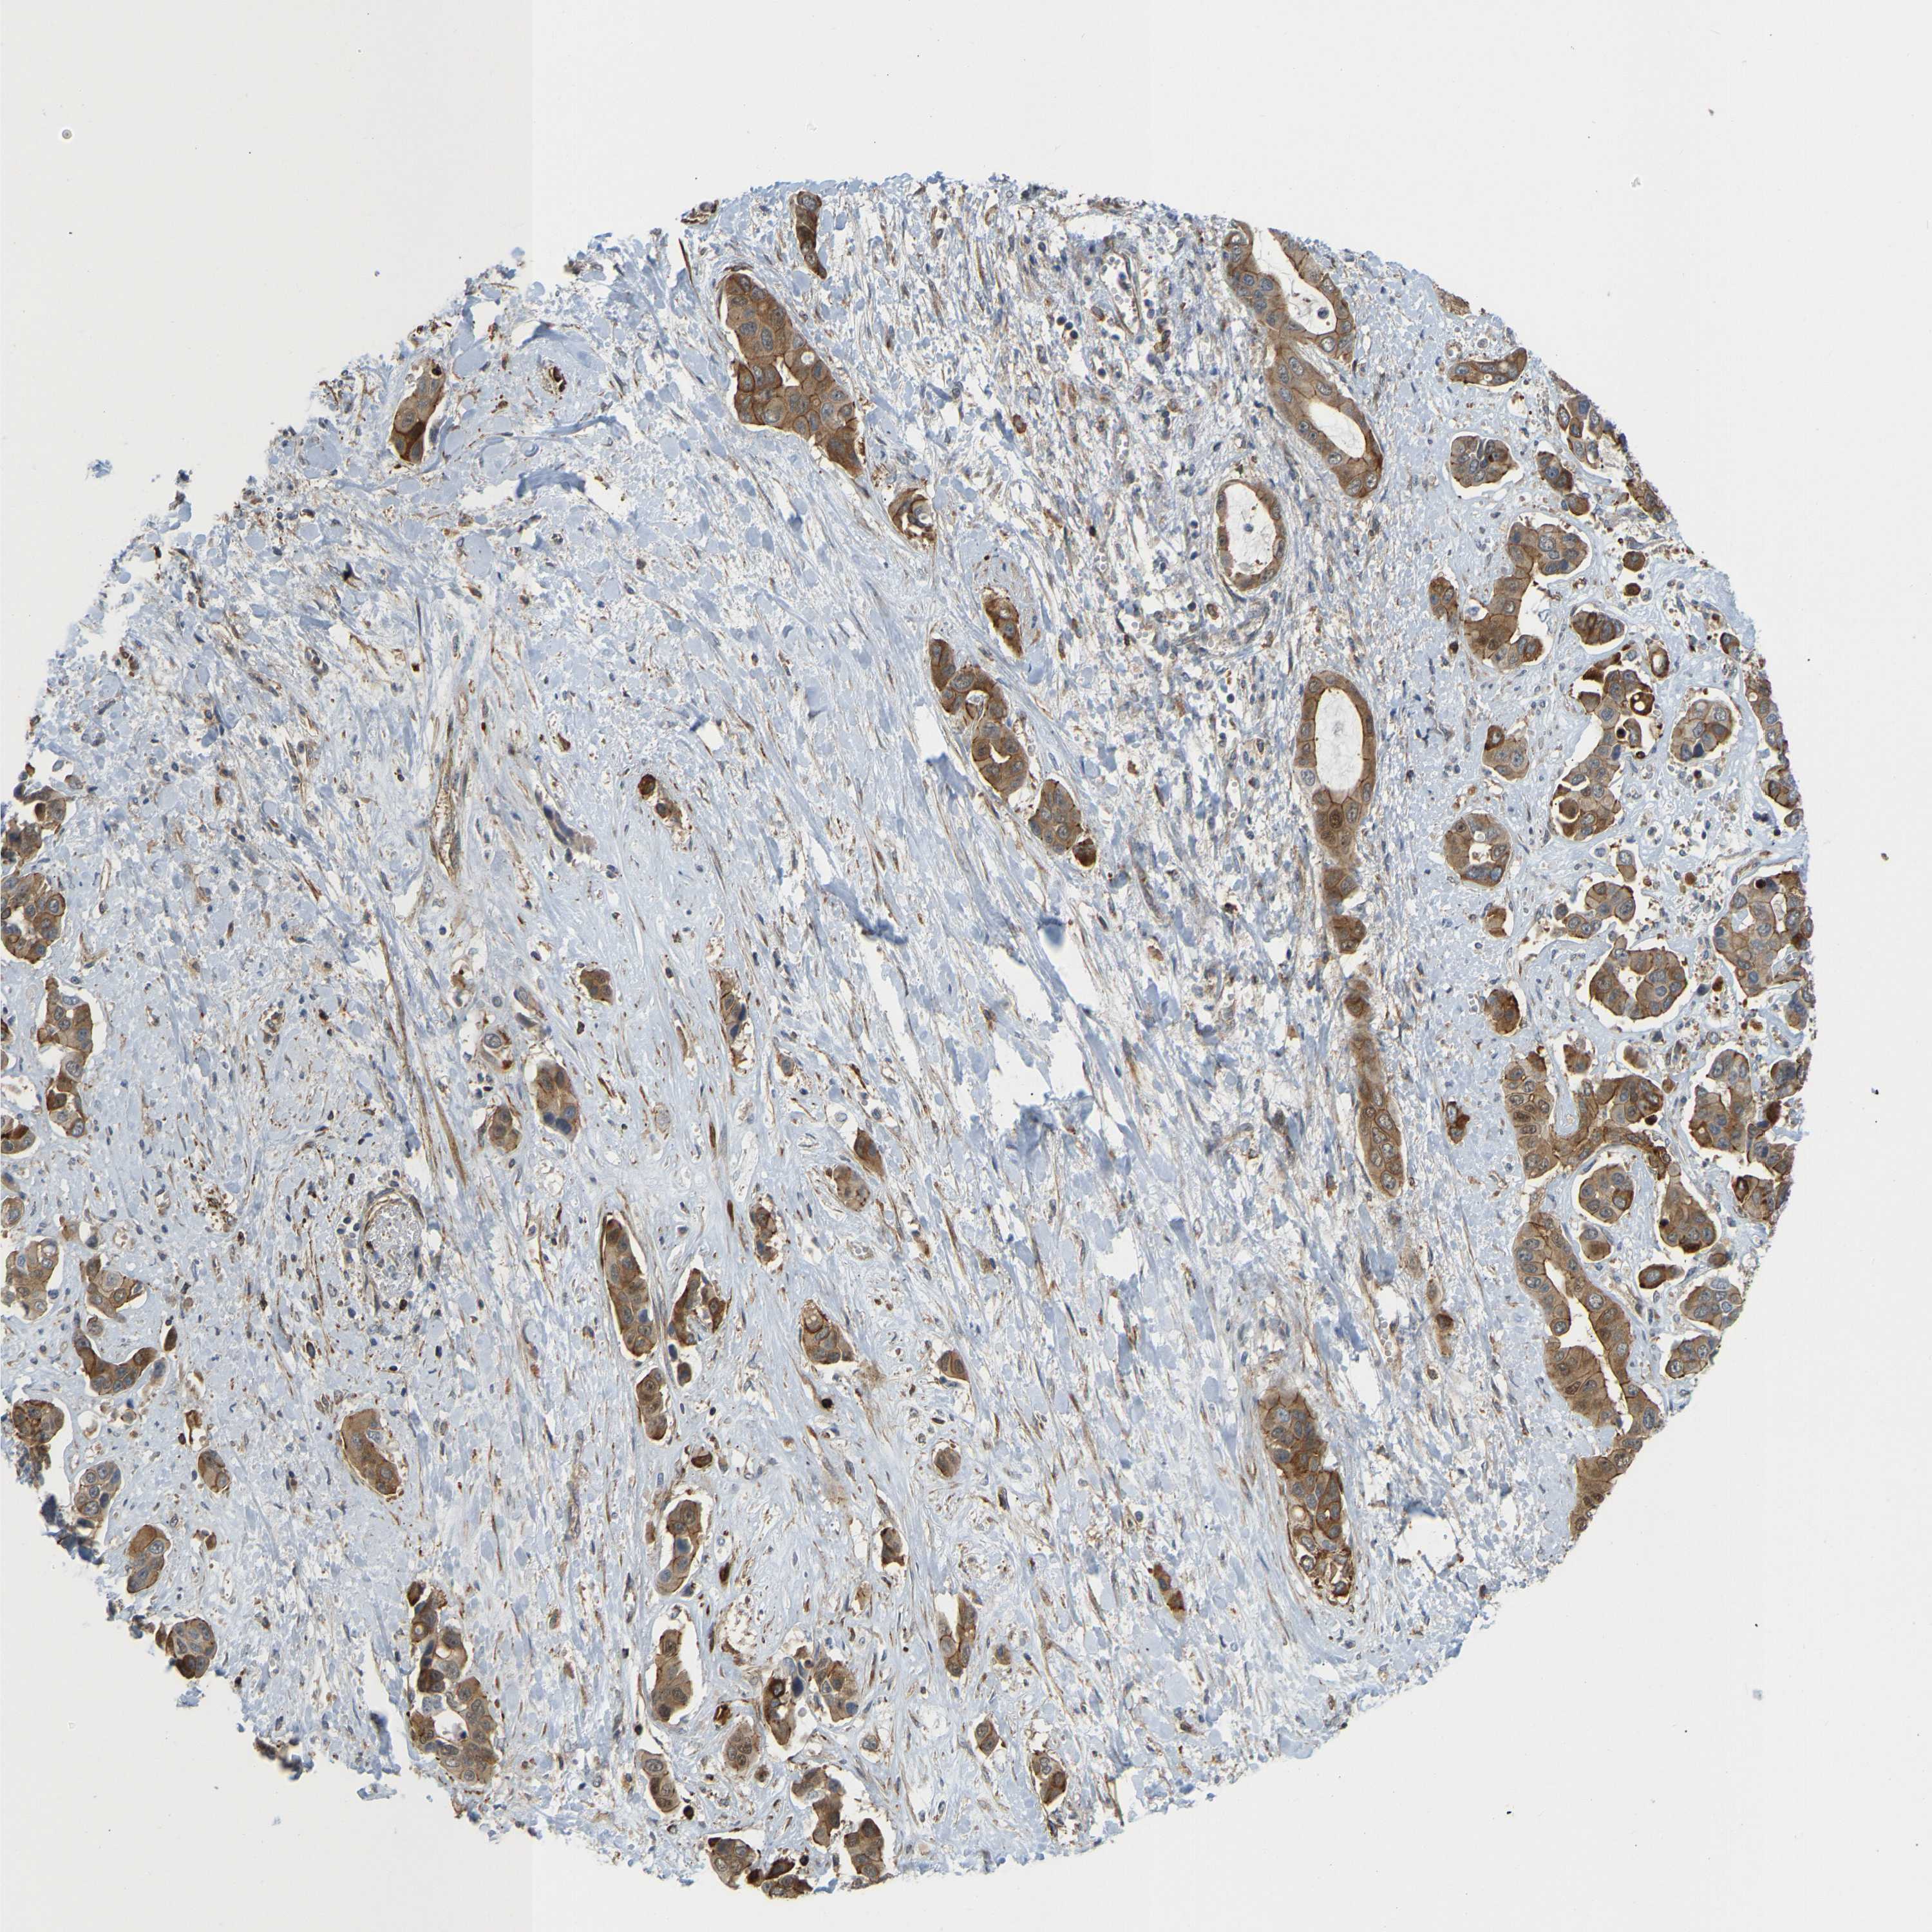

LIVER CANCER - Protein expressioni

A mouse-over function shows sample information and annotation data. Click on an image to view it in a full screen mode. Samples can be filtered based on level of antibody staining by selecting one or several of the following categories: high, medium, low and not detected. The assay and annotation is described here.

Note that samples used for immunohistochemistry by the Human Protein Atlas do not correspond to samples in the TCGA dataset.

Antibody stainingi

Antibody staining in the annotated cell types in the current human tissue is reported as not detected, low, medium, or high, based on conventional immunohistochemistry profiling in selected tissues. This score is based on the combination of the staining intensity and fraction of stained cells.

Each image is clickable and will lead to virtual microscopy that enables deeper exploration of all samples and also displays staining intensity scores, fraction scores and subcellular localization as well as patient and tissue information for each sample.

Antibody HPA018135

Staining

High

Medium

Low

Not detected

Intensity

Strong

Moderate

Weak

Negative

Quantity

>75%

75%-25%

<25%

None

Location

Nuclear

Cytoplasmic/membranous

Cytoplasmic/membranous,nuclear

Cholangiocarcinoma

Carcinoma, Hepatocellular, NOS